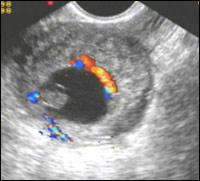

Обнаружение патологического образования в проекции придатков является наиболее точным из всех косвенных признаков. Данное образование представляет собой трубу с плодовместилещем. В тех случаях, когда имеется прогрессирующая трубная беременность малого срока, в просвете маточной трубы определяется полость амниона округло-овальной формы, внутри которой можно визуализировать желточный мешок в виде кольцевидной структуры. Особенностью визуализации плодного яйца в маточной трубе является хорошо определяемый хорион, который окружает полость амниона по периферии в виде ткани солидной структуры. Такая отчетливая визуализация хориона объясняется разной эхогенностью тканей. Если в полости матки трофобласт и эндометрий имеют одинаковые эхографические характеристики, то в просвете трубы, где слизистая очень тонкая, хорион хорошо определяется как зона повышенной эхогенности на гипоэхогенном фоне мышечного слоя стенки. Дополнительным эхогрфическим признаком является отсутствие связи выявленного образования с маткой и яичником, для чего помогает исследование имитации двуручного исследования. Применять этот прием следует очень осторожно, помня, что при форсированных движениях возможен разрыв трубы. Более щадящим методом, однако, менее надежным является глубокий вдох и выдох пациенткой, при котором происходит смещение внутренних органов.

Используя методику цветового картирования, в придатковом образовании определяется зона гиперваскуляризации, которая представляет собой трофобластический кровоток, отражающий интенсивное кровоснабжение эктопического эмбриона. Частота определения кровотока составляет 80-92 % случаев. Отсутствие визуализации трофобластического кровотока наблюдается при диаметре плодного яйца менее 10 мм или при прерывании беременности в малом сроке. По мере роста плодного яйца и пенетрации ворсин хориона в стенку маточной трубы начинает регистрироваться периферический кровоток с нарастающей интенсивностью, а в акушерском сроке беременности более 6 недель, имеется замкнутое кольцо из цветовых локусов.

Трофобластический артериальный кровоток при прогрессирующей трубной беременности характеризуется высокой конечно-диастолической скоростью, при этом отмечается низкорезистентный тип кривой скорости кровотока с тенденцией снижения численных значений ИР по мере увеличения срока беременности, показатели которых составляют 0,35-0,53.